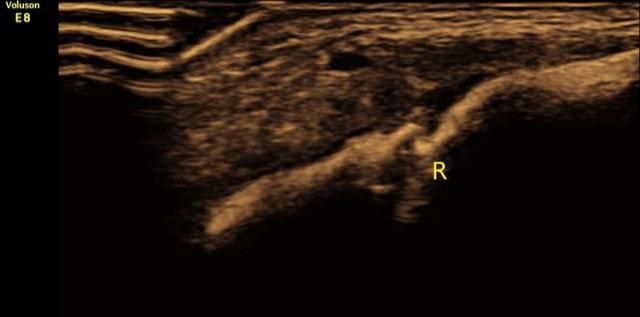

尽管如此,还是有很多家长担心X光的放射性,在选择拍X光片时常常忧心忡忡,因而可以选择超声诊断!超声检查作为最常用且最安全的一种临床诊断方法,它不仅无创、无痛、方便快捷又准确,还可以定期随访骨折的愈合情况。